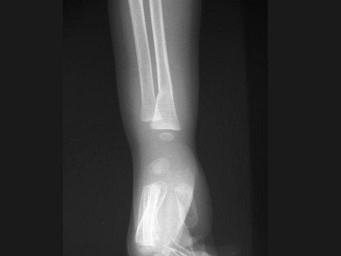

出生6个月的男婴,摔地后右手红肿,结合CR片,正确的骨折类型是?(?)A.青枝骨折B.横行骨折C.斜行骨折D.粉碎性骨折E.压缩骨折

问题 出生6个月的男婴,摔地后右手红肿,结合CR片,正确的骨折类型是?(?)

选项 A.青枝骨折 B.横行骨折 C.斜行骨折 D.粉碎性骨折 E.压缩骨折

答案 A